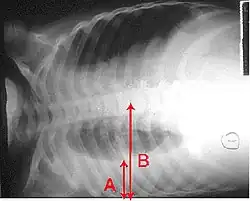

X-ray presentations of pneumonia may be classified as lobar pneumonia, bronchopneumonia, lobular pneumonia, and interstitial pneumonia.[75] Bacterial, community-acquired pneumonia classically show lung consolidation of one lung segmental lobe, which is known as lobar pneumonia.[42] However, findings may vary, and other patterns are common in other types of pneumonia.[42] Aspiration pneumonia may present with bilateral opacities primarily in the bases of the lungs and on the right side.[42] Radiographs of viral pneumonia may appear normal, appear hyper-inflated, have bilateral patchy areas, or present similar to bacterial pneumonia with lobar consolidation.[42] Radiologic findings may not be present in the early stages of the disease, especially in the presence of dehydration, or may be difficult to interpret in the obese or those with a history of lung disease.[24] Complications such as pleural effusion may also be found on chest radiographs. Laterolateral chest radiographs can increase the diagnostic accuracy of lung consolidation and pleural effusion.[41]

Right middle lobe pneumonia in a child as seen on plain X-ray